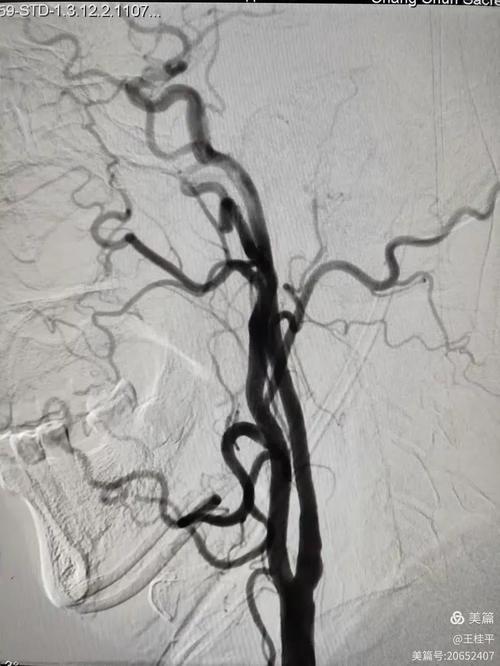

- 头颅CTA/MRA/DSA:必要时(如症状变化、评估是否需要手术)进行脑血管成像,精确评估狭窄部位和程度。

第四支柱:评估是否需要介入或手术治疗(二线方案)

对于药物治疗后仍反复发作,或狭窄程度非常严重(如超过70%)的高危患者,医生可能会建议进行介入或手术治疗。